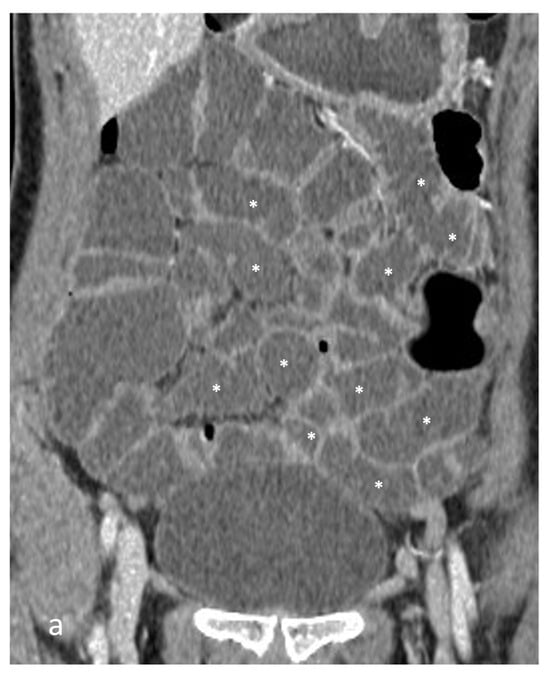

- A normal bowel loop caliber ranges between 2 and 2.5 cm. A bowel lumen is dilated when it has a maximum diameter greater than 2.5–3 cm. The dilation is mild when the upstream lumen is dilated up to 4 cm and severe when it is more than 4 cm (Figure 3) [24]. Pre-stenotic bowel dilatation should always be checked, as it is a sign related to bowel obstruction. Moderate to severe stenosis was determined via double-contrast imaging (conventional barium study) with a sufficient amount of injected air, and stenosis was defined as stenosis in which the lumen was less than one half that of neighboring healthy intestine [25].